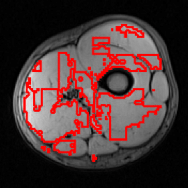

Refer to caption

Figure 4: Examples of AdaBoost muscle tissue segmentation results.

Mean and standard deviation of the mentioned performance measures were taken over a 10-fold cross-validation, and are presented in Fig. 3. Segmentation of the whole muscle region (Fig. 4) yielded mean Recall, Precision and Dice overlap coefficients of 0.81500.81500.8150, 0.74540.74540.7454 and 0.76230.76230.7623, respectively.

These reported results indicate the method efficiency, particularly for the retrieval of true positive occurrences. It should be noted that the AdaBoost algorithm was trained with a downsampled ground truth mask to address the descriptor resolution. However, performance was measured considering the normal resolution ground truth mask.

Average performance measures scored above 0.70.70.7, despite the variability on the results (Fig. 3). From the total 50 AdaBoost results obtained in cross-validation, the majority presented a correct identification of the muscle region, with proper tissue separation. Results with high recall rates tend to also increase the number of false positives (lower precision), as the example shown in Fig. 4(a). Using more features could improve the discriminative properties of the proposed classification scheme.

On the other hand, in some cases, the texture recognition failed to provide accurate results, as shown in Fig. 4(b), leading to low recall values. This figure shows the worst obtained result (corresponding to volume 10 in Fig. 3). An objective quality study may help to bring insight into a possible impact of texture quality on the recall rate of the proposed segmentation model.